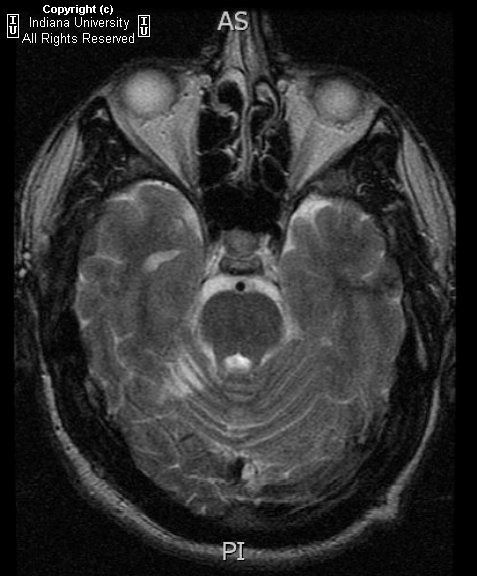

小脑发育不良性神经节细胞瘤!

小脑皮质弥漫性神经节细胞瘤